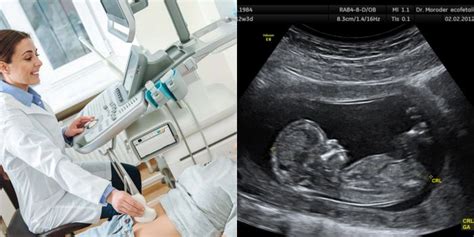

Nėštumo laikotarpis - tai laukimo ir pokyčių metas, o viena iš svarbiausių datų besilaukiančioms poroms yra numatyta gimdymo data. Tačiau svarbu suprasti, kad ši data dažniausiai yra tik apytikslė, o tiksliai ją nustatyti gali būti sudėtinga. Įprastai nėštumas trunka 40 savaičių arba 280 dienų, o skaičiuojant nuo kiaušinėlio apvaisinimo - 267 d. Bet visiškai normalu, jei vaikelis gimsta ir 38 ar 42 nėštumo savaitę. Beveik visais atvejais gimdymo data tik apytikslė.

Tradicinis metodas, naudojamas preliminariai gimdymo datai nustatyti, remiasi moters mėnesinių ciklu. Šis metodas yra plačiai taikomas medicininėje praktikoje ir padeda nustatyti apytikslį laikotarpį, kada galima tikėtis vaikelio gimimo.